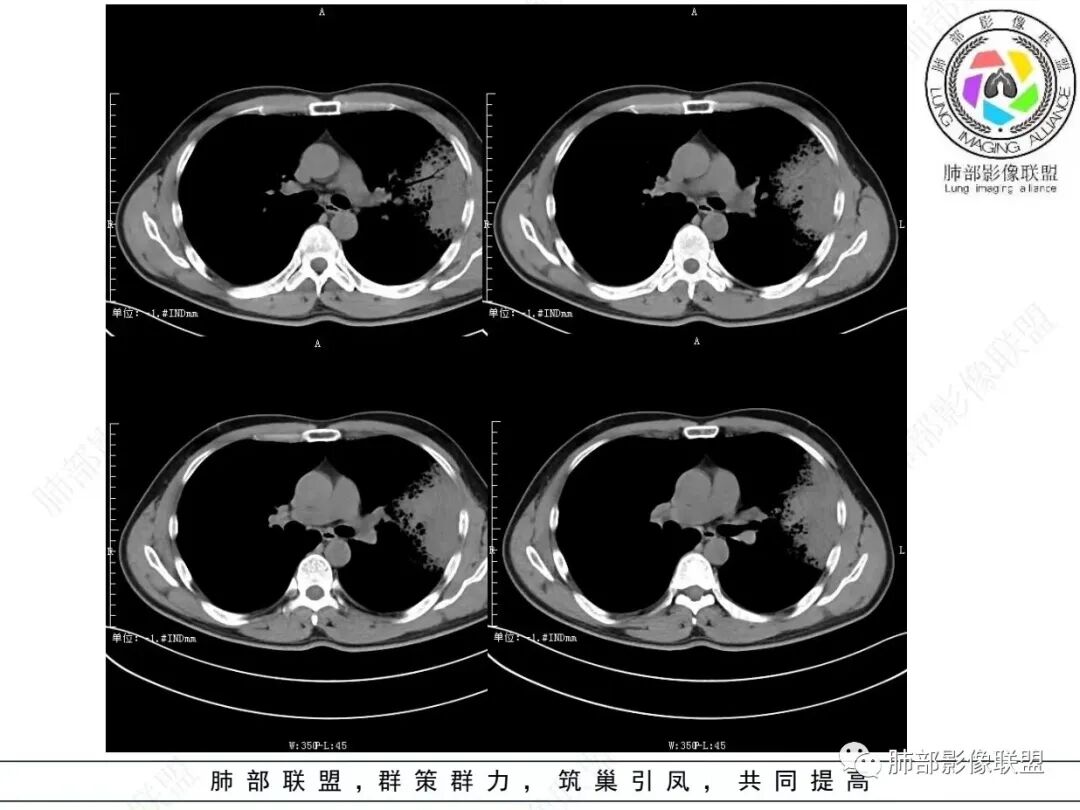

左肺上叶大片状实变影混合磨玻璃影,其内可见蜂窝征,增强扫描明显强化,进入病灶血管边缘有侵犯,结合病史,考虑肺炎型肺癌。鉴别诊断大叶性肺炎。

中年男性,咳嗽咳血,影像表现左肺上叶片状阴影,周围可见多发磨玻璃影,病灶内支气管僵硬,增强病灶内可见血管造影征,病灶与胸膜可见栽赃,考虑恶性病变,粘液性腺癌。

左肺上叶胸膜下实变伴周围边缘磨玻璃,其内可见枯枝征及蜂窝,不均匀强化,可见低密度影,血管显示尚可,考虑肺炎型肺腺癌

左肺大片实变,密度不均,边缘膨隆,周围磨玻璃,强化密度略低,双肺小结节,考虑粘液腺癌

左肺上叶胸膜下大片状实变区,周围散在磨玻璃影,局部膨隆,界清,近端气管截断,叶间胸膜局部稍膨隆,增强扫描实变区轻度强化,内走形血管僵硬,轮廓毛糙,胸膜栽赃,半年病史考虑恶性,粘液性腺癌

左肺上叶大片状实变密度影,边缘见磨玻璃密度,呈外向内生长,内可见多发支气管影,走行僵直,增强后实变部分明显不均匀强化,血管纤细,考虑粘液腺癌可能大

男,46岁,反复咳嗽半年,痰中带血,加重10天,左肺上叶大片状实变影,边缘模糊,病灶内见蜂窝影及僵硬支气管,双肺内见多发小结节,增强扫描,病灶明显强化,左侧胸壁增厚,考虑恶性病变,粘液性腺癌可能。

左肺上叶斑片实变影,内有周边磨玻璃影并小叶内间质增厚,增强实变影内有肺动脉走形,考虑肺炎型肺癌;双肺弥漫分布小结节,细支气管炎?过敏性肺炎?转移?

左肺上叶片状实变,内可见多发空泡及蜂窝影,斜裂上方可见相同病灶由于斜裂阻挡呈重力分布,强化可见血管造影征,双肺弥漫分布气腔结节,临床咳白色粘液痰,考虑粘液腺癌

左上叶大片实变,实变以网格为中心,外向内生长,边界似清非清,实变内见枯树枝征及血管造影征,慢性病史,咳白色粘液痰,炎性标志物基本正常,定性恶性,考虑粘液腺癌

男,46,咳嗽半年,加重10天,白粘痰,偶有痰血。胸部CT:左肺上叶舌叶大片实变影,边缘GGO,长轴沿胸膜及叶裂展开,重力依赖,胸膜叶裂阻隔,内见蜂窝,钱币征,枯枝。强化不均匀,血管造影征。考虑粘液腺癌,鉴别大叶性肺炎、干酪性肺炎等。

实变区内有低密度带,强化偏低,欠均匀

血管走形尚自然,没重建血管,没有明显血管受侵

2.左肺上叶大片状混合密度影,未见空洞,实变影主要位于胸膜下,长轴与胸膜平行,实变区内部密度不均、其内可见多发小斑片状低密度影,磨玻璃影多位居肺门一侧,可见网格,磨玻璃影边界多可分辨,重力分布趋势。病灶区支气管显示较为通畅,进入外围实变区渐至消隐。病灶轻度不均匀低强化,病灶区肺动脉显示较良好,未见破坏。